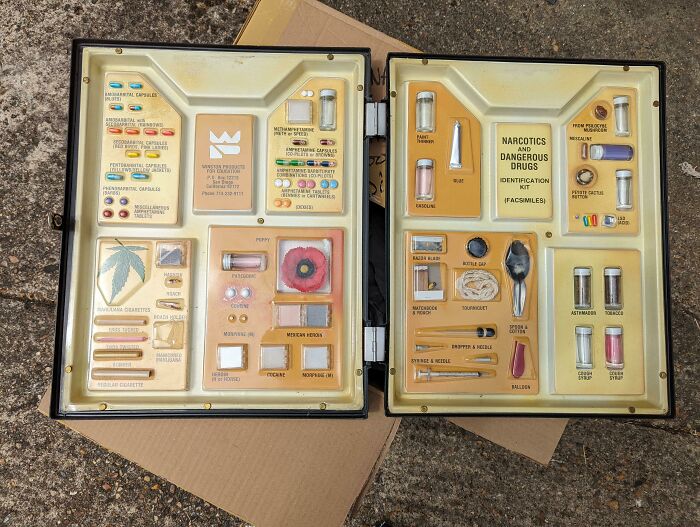

#130 Old School Drug Identification Kit Used To Train Customs Officials In Dubai, Neighbour Found In Some Old Boxes

Image credits: Mr-Bloke